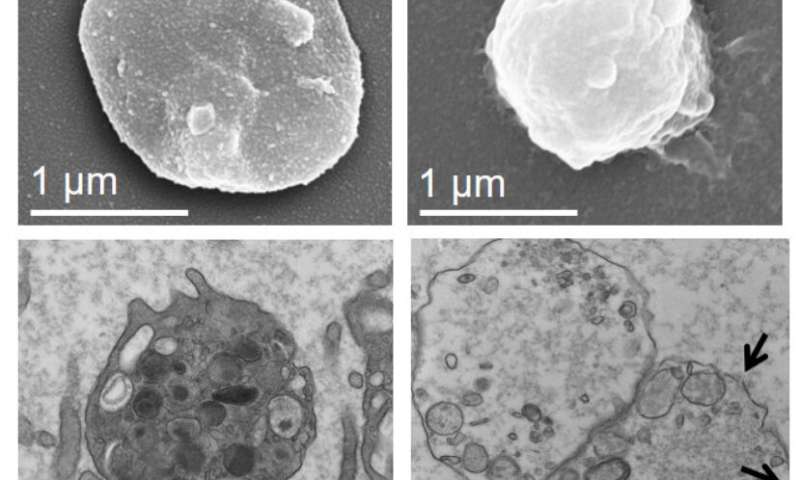

Immagine, un confronto affiancato di una piastrina normale (a sinistra) e l’esca piastrinica (a destra) sotto il microscopio. Credito: A.-L. Papa et al., Science Translational Medicine (2018).

Le esche sono piastrine umane le cui membrane lipidiche esterne e il contenuto interno sono stati rimossi in laboratorio tramite centrifugazione e trattamento con un detergente. Poiché sono essenzialmente vuote, queste esche sono circa un terzo delle dimensioni delle piastrine normali, ma conservano la maggior parte delle proteine adesive sulle loro superfici. Queste esche possono ancora utilizzare queste molecole di superficie per legarsi ad altre cellule che si trovano naturalmente nel flusso sanguigno, ma non sono in grado di attivare il processo di coagulazione.